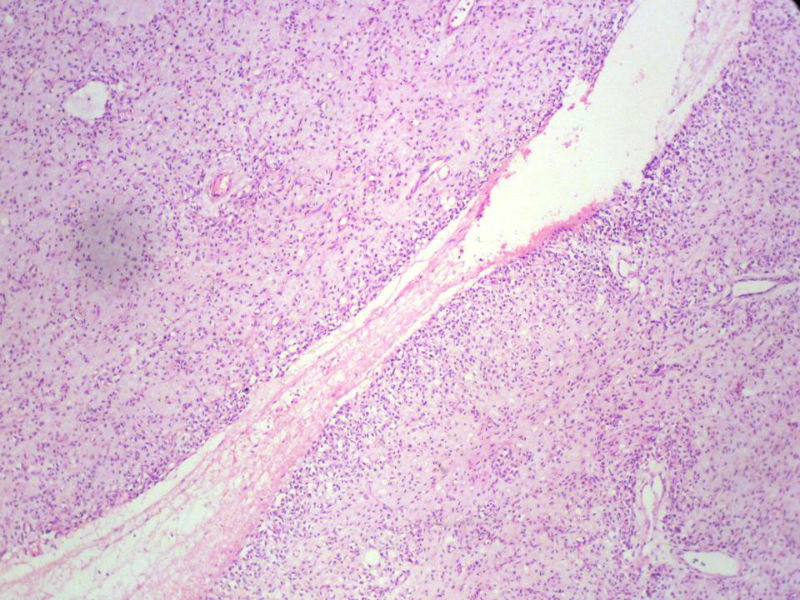

男,27岁,右股骨上段皮下肿物1年余,无明显疼痛,检查肿物明显隆起于皮下,边界清楚,手术完整切除肿物。肉眼,肿物6X6X5厘米,外观多结节状,似有包膜,切面灰白色,质韧。

特别提示:镜下核分裂3-4/HP.

3. 本例组织学改变与粘液性脂肪肉瘤,粘液样纤维肉瘤,纤维粘液样肉瘤,骨外粘液样软骨肉瘤都有重叠之处,且镜下并未见典型结构。由此,免疫组化结果就尤显重要。特别是专业书籍提到,突触素或嗜铬素阳性,对鉴别诊断有重要意义。我用CGA,也是在以上几个肿瘤中举棋不定而为。NSE和CK没用,其实我想用更多的抗体来证实更多的东西,但患者的经济条件不太好,遗憾!